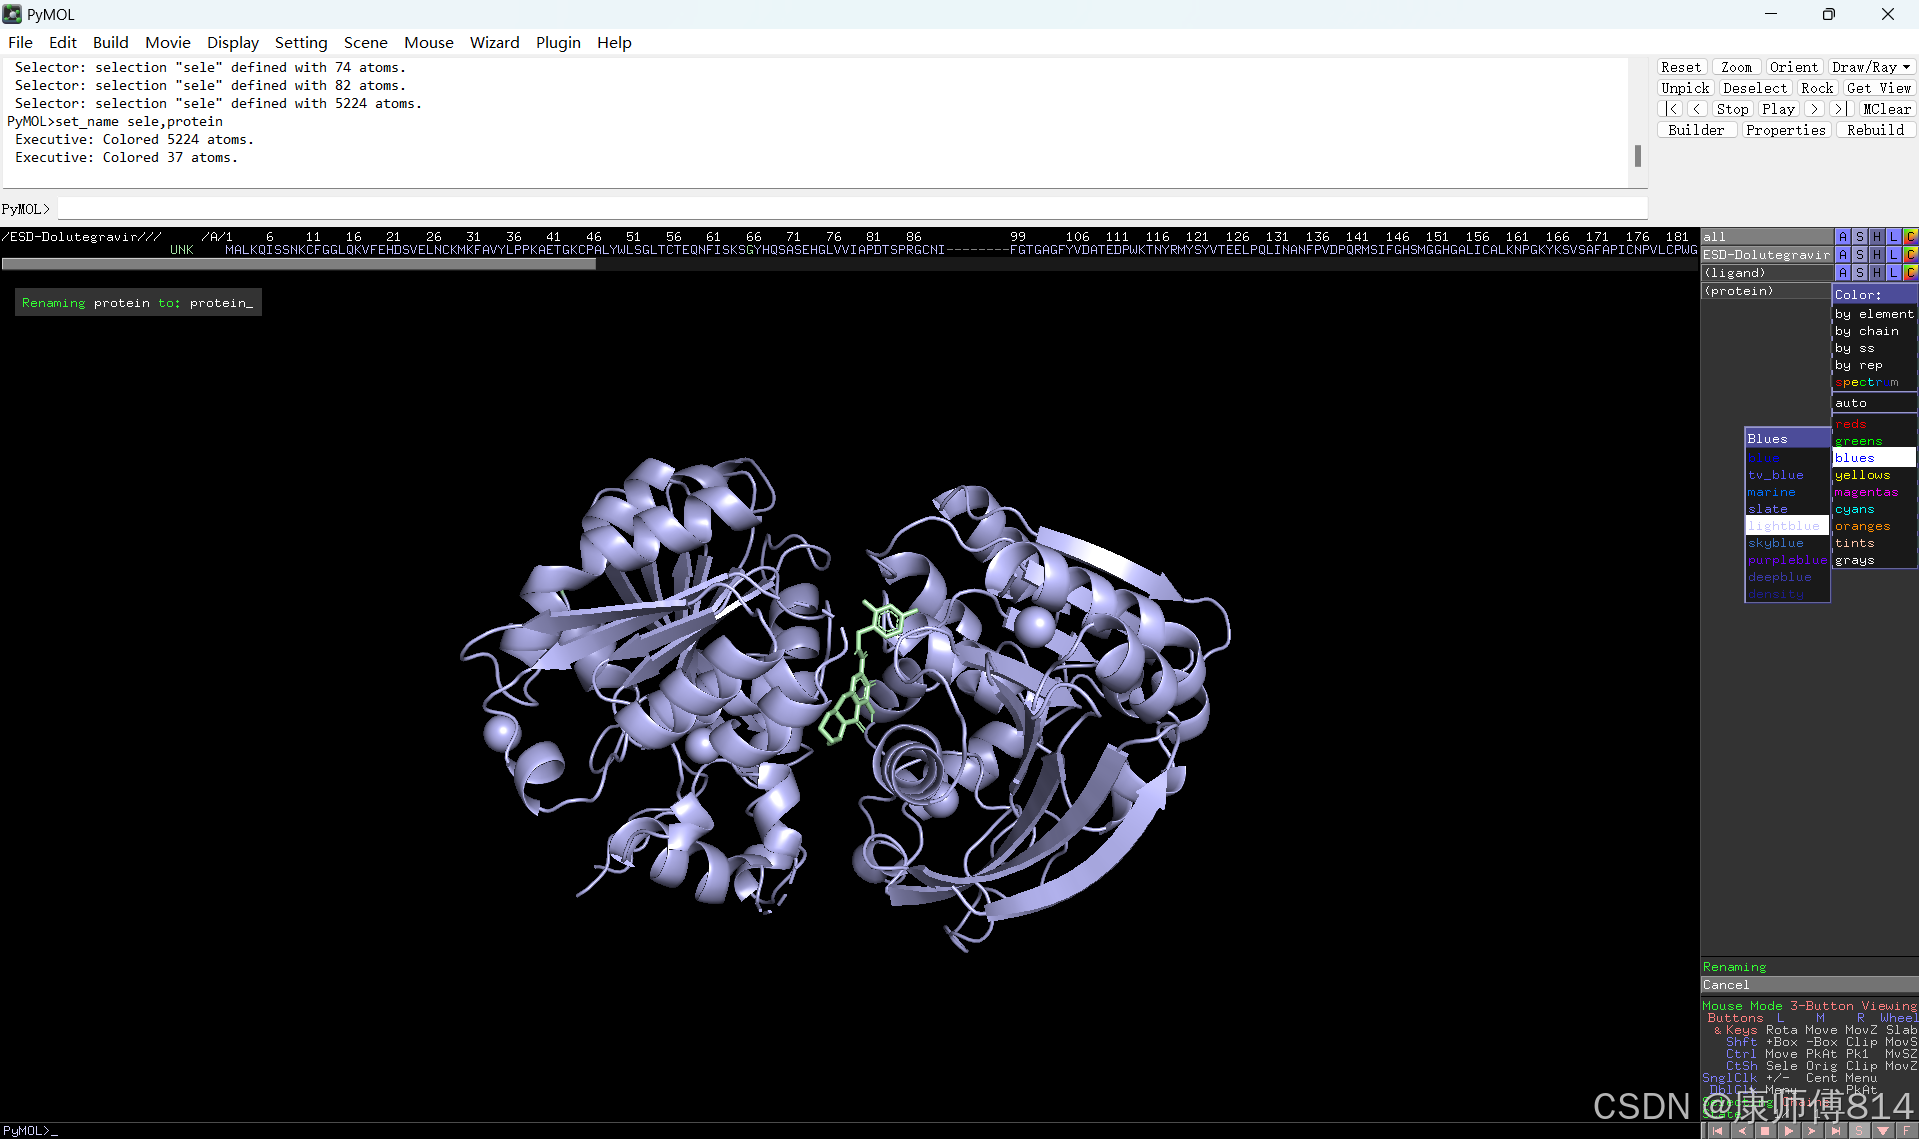

#在pymol中打开刚才得到的pdb文件,点击右下角S打开序列,选中小分子序列,命名为ligand。

#同样选中蛋白质序列,先将右下角Selecing选为Chains,然后才能悬着呢全部蛋白质序列(如果是多聚体蛋白,按住shift以连续选中多条链),命名为protein

#点击蛋白和小分子后的C按钮可以修改颜色

#选中小分子,按以下顺序点击以显示结合位点的氢键